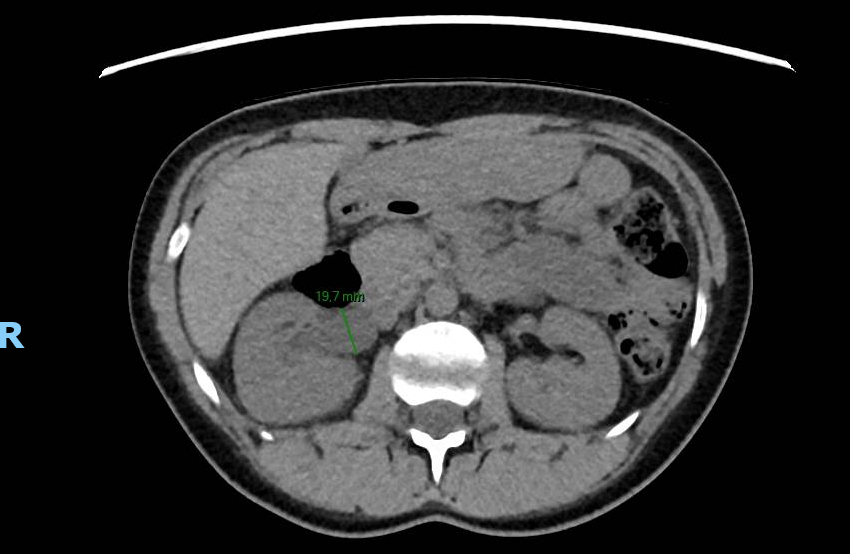

Le CT-scanner réalisé devant une colique néphrétique montre une compression urétérale droite extrinsèque sur une cup menstruelle. Cette dernière est retirée améliorant rapidement les douleurs.

Il existe 5 cas similaires publiés entre 2018 et 2020 (1), tous concernant l’uretère droit. Une étude ex-vivo comparant 14 marques de cup, de tailles et formes différents, a démontré qu’une cup trop grande ou trop rigide pouvait être la cause d’une compression des voies urinaires, en plus d’un inconfort (2).

Ce cas et la littérature qui y est liée démontre l’importance d’exclure la présence d’une cup en cas de colique néphrétique chez les femmes pré-ménopausées.